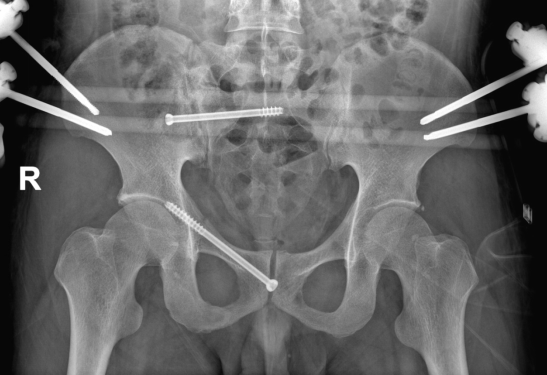

术前CT示骨盆完整性被破坏

患者右侧骶骨骨折+右侧耻骨上下支骨折,已经影响到骨盆环的稳定。经骨伤科主任张成勇、副主任许锦涛团队通过充分讨论后,决定为其在全麻下,行骨盆骨折前环逆行耻骨螺钉内固定+外固定架、骨盆骨折后环骶髂关节螺钉内固定术,征询患者及家属同意后,在西部战区总医院骨科廖冬发教授的指导下,顺利完成手术。

术中两处切口均不到3厘米,臀部切口仅1厘米,术中出血约50毫升,目前患者恢复良好。

术后X片